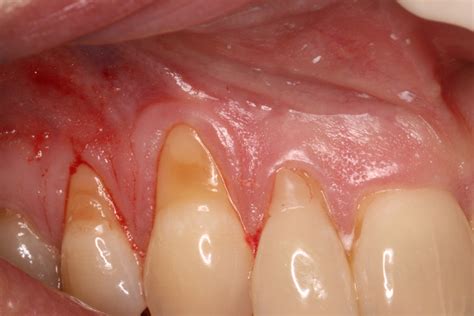

Gum sensitivity is exactly what it sounds like – some form of irritation originating from the gums. If you think your gums are sensitive, look for some very specific symptoms to be sure: Gum sensitivity can result from gingivitis, the initial stage of gum disease or from local irritation such as food impaction.

Gum tissue is not immune to problems, particularly disease and irritation that can make gum tissue sensitive and painful. What exactly can cause gum sensitivity and what will help it go away?

If you have sensitive gums, you might notice soreness whenever you brush or floss your teeth. The pain may gradually subside or linger. Sometimes, sensitive gums are accompanied by: Keep in mind that there’s a difference between tooth sensitivity and gum sensitivity.